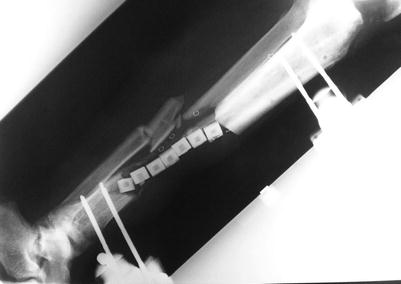

Fig. 23.14

Procedure 14: Appearance of transplanted bone fixed in place